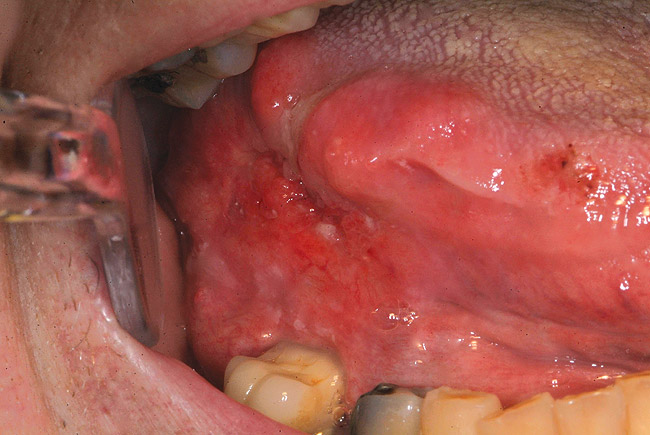

Clinically, it was thought that early prototypical OPSCC and OCSCC had identical potentially malignant (premalignant) appearing lesions—leukoplakia, erythroplakia, or erythroleukoplakia (Figure 3). Studies have shown that the erythroplakic component is most likely to microscopically demonstrate significant amounts of epithelial dysplasia.8 Painless, ulcerative lesions then develop from the potentially malignant lesions and slowly enlarge until additional signs and symptoms appear (Figure 4), and eventually, if the lesion remains undiagnosed, locoregional cervical lymphadenopathy becomes apparent. Unfortunately, researchers have recently discovered that clinical, normal-appearing mucosa of the oral cavity and oropharynx can already harbor microscopic and molecular precancerous changes.1 Furthermore, a defined, observable clinical precursor lesion associated with oropharyngeal squamous cell carcinoma caused by HPV infection is not yet known.

Figure 4  Erythroplakia biopsied and diagnosed as squamous cell carcinoma of the lingual tonsil area.)

Figure 4